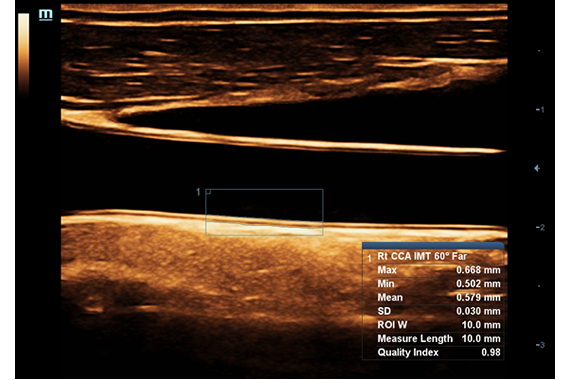

Mindray의 독자적인 3T 테크놀로지(Triple-matching layers, Total-cut design, Thermal control) 와 조합하면 새로운 싱글 크리스탈의 컨벡스와 심장 프로브는 보다 넓은 대역폭을 제공하고, 보다 뛰어난 투과성과 높은 해상도를 동시에 제공하기 위해 최적의 검사를 실현하여 산과/부인과, 복부, 심혈관계 등의 넓은 길을 제공해줍니다.